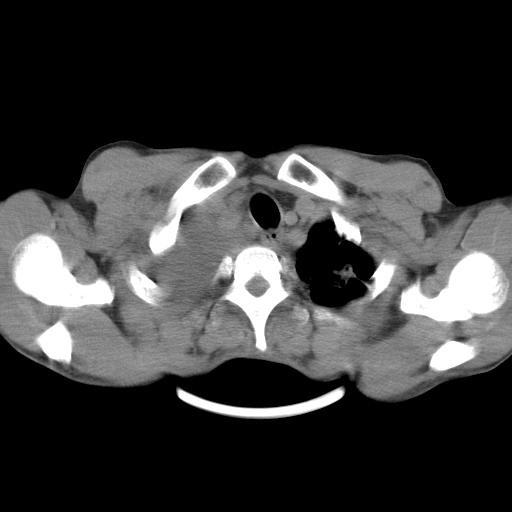

男性,44岁,结核病史多年。现胸闷气短,咳嗽,偶咳血。

双肺多发结节影最分空洞形成考虑占位不除外结核

1、右侧大量胸腔积液伴右肺压缩性膨胀不全,建议抽液治疗后复查 2、两肺继发性tb伴空洞形成。

1)两肺继发性肺结核伴空洞形成,左肺多发性结核球。2)右侧大量胸腔积液伴右肺部分膨胀不全。3)纵隔淋巴结肿大。

1,双肺多发结节 并空洞影改变, 左侧胸腔积液并部分包裹, 结合原病史首先考虑结核. 但也不除外其它.

2,左侧有一根肋骨陈旧性骨折? 建议追查 .

吉大一院胸水抽检结果:结核性胸水